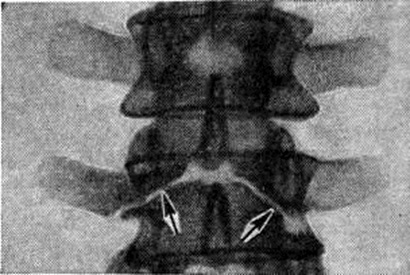

Рис. 3.

Томограмма части поясничного отдела позвоночника при spina bifida anterior (прямая проекция): тела III и IV поясничных позвонков имеют широкие передние расщелины (указаны стрелками).